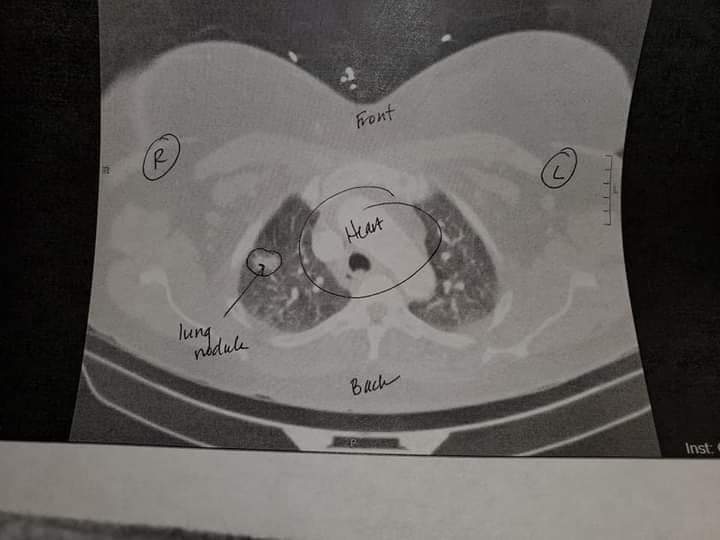

No Heels to Heal started in twenty twenty from total knee replacements that I had on my knees at that time it was about healing from that. I was diagnose with stage 4 lung cancer who ever knew that I had a mass sitting on my lungs walking in my first show after the show I was hospitalized to get the mass removed at that time I only needed the chemo treatments. When I was planning my second show I turned it around and made it about healing from something because we all have been healed or delivered from something. The models created a poster board of what they were healed from I knew this journey wasn’t about me it was being a blessing to others letting them know if God delivered me he can do the same for you. The second show I had a poster board of my total knee replacements and being healed from cancer. The show is about healing this is the vision God gave me and every year I put on this amazing show to inspire others I’m a testimony of what God can do. This year will be show number 8 cancer free again its not about me it’s what God is doing in my life for others to see he can do the same for you.

No this has not been a smooth road. I have been dealing with cancer since 2020. I was diagnosed with stage 4, lung cancer was cancer free two years then October 2025 cancer came back now going through chemo and radiation it has been a journey